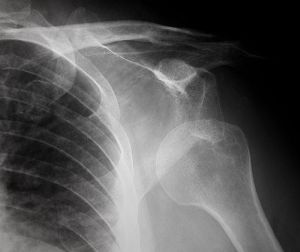

Εξατομικευμένη αρθροπλαστική του ώμου

Η αρθροπλαστική του ώμου, η αντικατάσταση δηλαδή της άρθρωσης του ώμου με την τοποθέτηση τεχνητών εμφυτευμάτων (κράματα μετάλλου και ειδικών συνθετικών υλικών) επιλέγεται σε περιπτώσεις προχωρημένης αρθρίτιδας η οποία δεν ανακουφίζεται σε συντηρητικά μέσα (φυσιοθεραπεία, αντιφλεγμονώδη φάρμακα, άσκηση, εγχύσεις).

Η εξατομικευμένη αρθροπλαστική του ώμου είναι μια σύγχρονη προσέγγιση στη χειρουργική αντικατάσταση του ώμου, σχεδιασμένη για να παρέχει την υψηλότερη δυνατή ποιότητα και ακρίβεια στην επέμβαση.

O γιατρός λαμβάνει υπόψη τις ιδιαιτερότητες, τις απαιτήσεις και τα μοναδικά ανατομικά χαρακτηριστικά του κάθε ασθενή και εν συνεχεία προβαίνει στην επιλογή των κατάλληλων υλικών και χειρουργικών τεχνικών για την πραγματοποίηση της επέμβασης.

Με την εξατομικευμένη προσέγγιση, και τα σύγχρονα πρωτόκολλα αντιμετώπισης του μετεγχειρητικού πόνου, επιτρέπεται η άμεση προσεκτική κινητοποίηση του άνω άκρου, η περίοδος παραμονής στην κλινική είναι μικρότερη, και η ανάρρωση ταχύτερη.